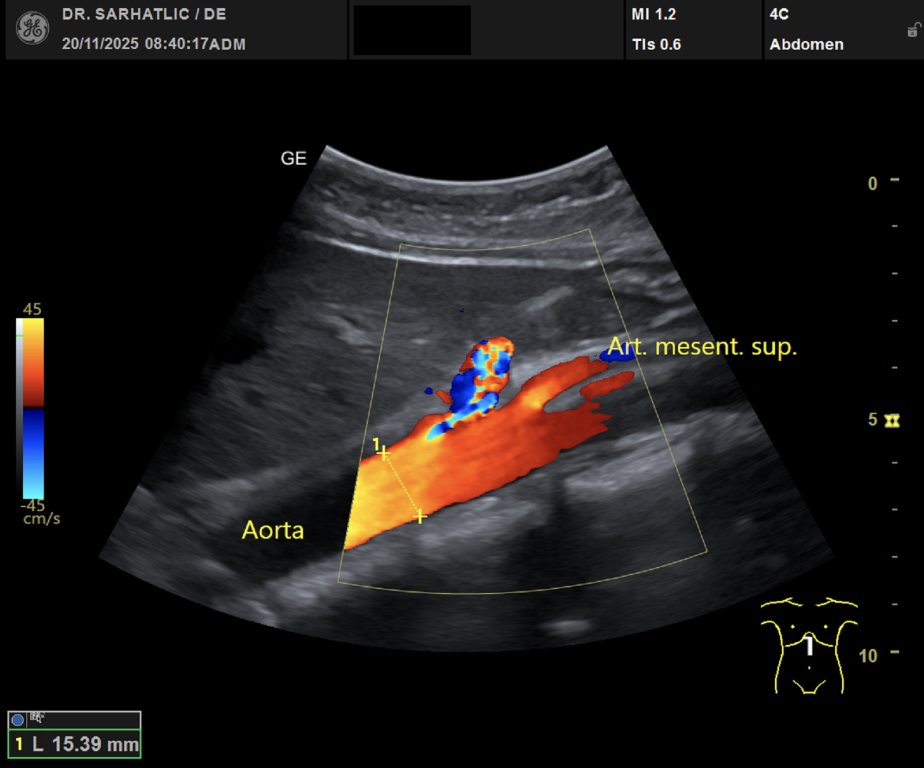

MODERNE ULTRASCHALLDIAGNOSTIK- Modernes Farbdoppler-Ultraschallgerät

- Hochauflösende Schallköpfe

- Detaillierte Organuntersuchungen

- Ultraschall aller inneren Organe (z. B. Leber, Bauchspeicheldrüse, Nieren, Prostata, Schilddrüse)